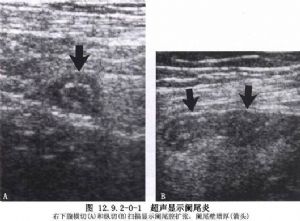

急性阑尾炎是小儿最常见的急腹症。由于小儿阑尾壁薄,穿孔率高;腹腔对感染的局限能力差,一旦穿孔常造成弥漫性腹膜炎;同时小儿又多因诊断延误而未能早期治疗,所以临床所见小儿阑尾炎病情较重。因此,小儿阑尾炎一旦确诊,应立即手术治疗(图12.9.2-0-1)。